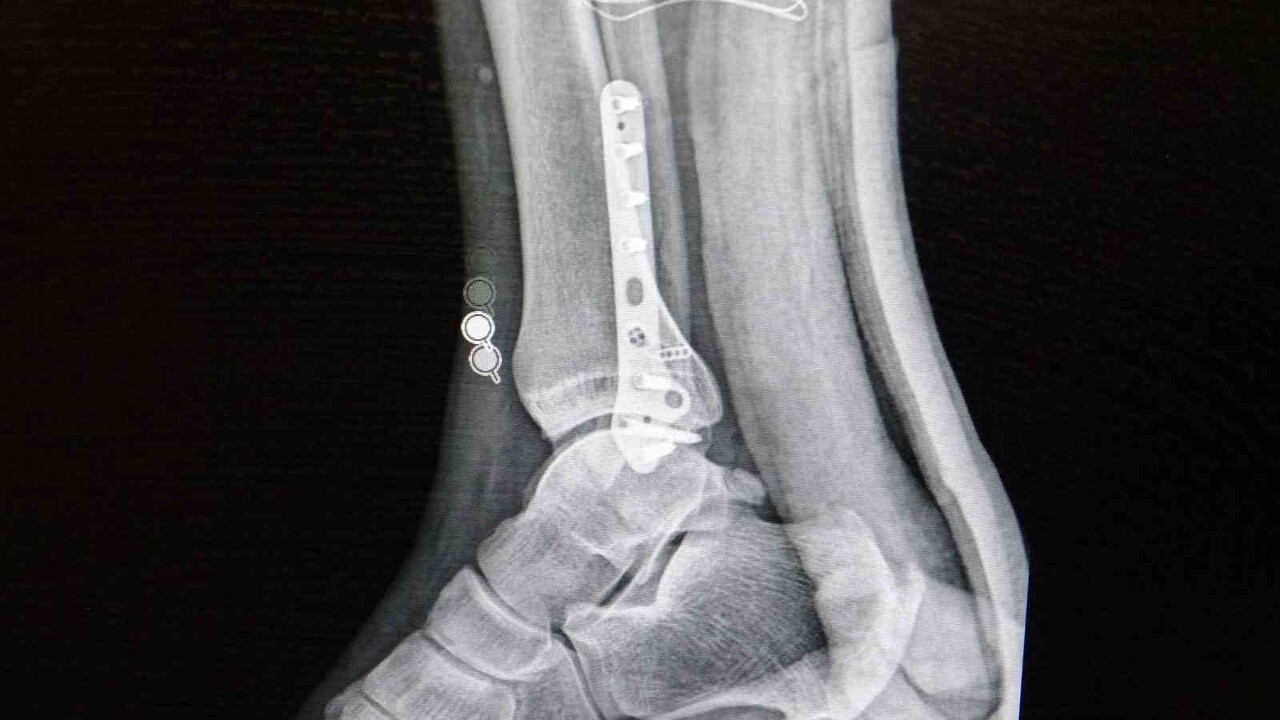

Ortopedi polikliniklerine en sık ayak bileği, diz ve omuz yaralanmalarıyla başvurulduğunu belirten Demirbaş, futbol nedeniyle yaralanma oranlarının ilk sırada olduğunu aktardı. Futbolda menisküs yırtıkları, ön çapraz bağ yırtıkları, iç ve dış yan bağ yaralanmaları, aşil tendon kopmaları ve ayak bileği bağ yaralanmalarının sık görüldüğünü dile getirdi. Ayrıca spora bağlı kırıkların da önemli yer tuttuğunu belirtti.